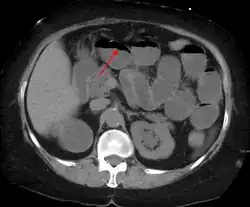

A small bowel obstruction as seen on CT

The main diagnostic tools are blood tests, X-rays of the abdomen, CT scanning, and ultrasound. If a mass is identified, biopsy may determine the nature of the mass.

Radiological signs of bowel obstruction include bowel distension (small bowel loops dilated >3 cm) and the presence of multiple (more than 2) air-fluid levels on supine and erect abdominal radiographs.[16] Ultrasounds may be as useful as CT scanning to make the diagnosis.[17]

Contrast enema or small bowel series or CT scan can be used to define the level of obstruction, whether the obstruction is partial or complete, and to help define the cause of the obstruction. The appearance of water-soluble contrast in the cecum on an abdominal radiograph within 24 hours of it being given by mouth predicts resolution of an adhesive small bowel obstruction with sensitivity of 97% and specificity of 96%.[18]